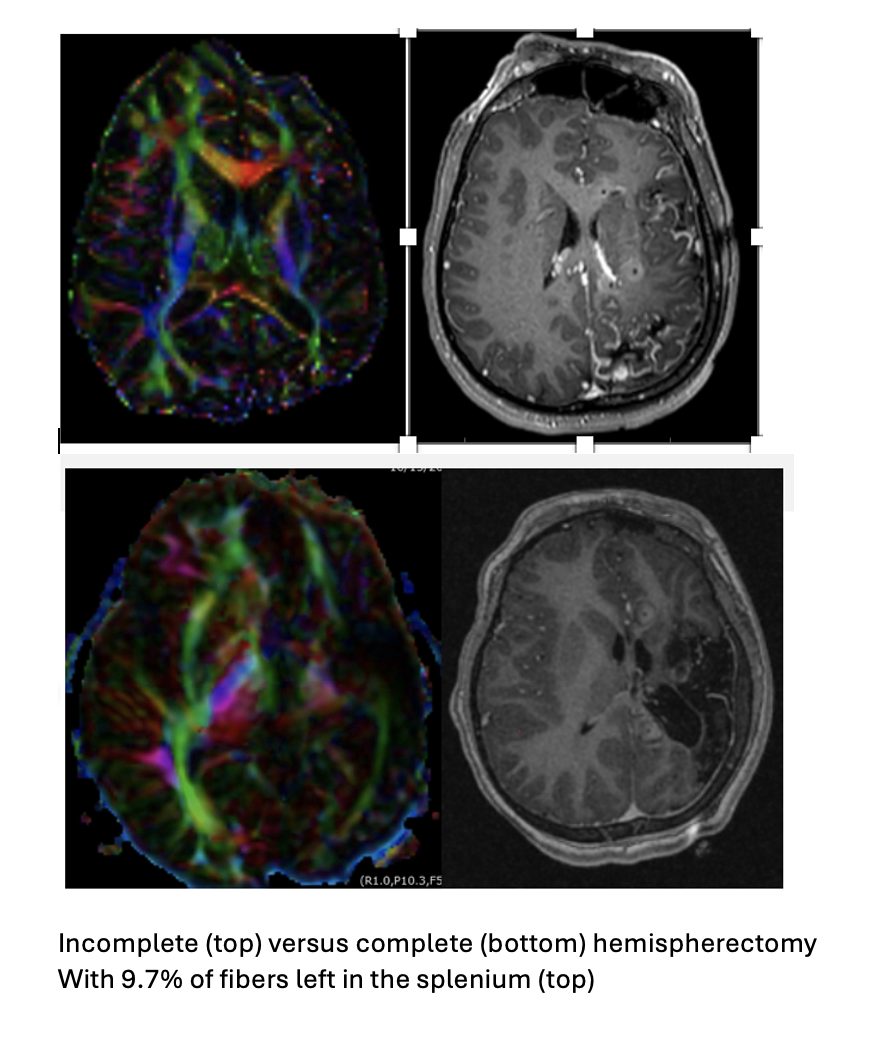

12 patients underwent an interstital laser hemispherectomy with a median follow-up of 2.0+0.8 years. Pathologies include perinatal  and early childhood strokes as well as Sturge-Weber. 10 out of 12 patients had an Engel class I outcome with a median disconnection of 90+8.9% of all string-containing voxels in interhemispheric tracts. Only two asymptomatic hemorrhages were observed and median hospital stay was 2.1 days. TBSS showed that both patients who were not seizure-free had a remaining cluster in the splenium and the uncinate of 8.3 and 9.7% respectively compared to the rest with remaining clusters of 2.1+0.7% (p< 0.0001) and correspondingly FA maps showed a significantly higher delta value in the  seizure-free  group (p< 0.00001) . Measuring the distance between perceived anatomic tracts based on MR morphology and actual tracts identified by DTI showed up to 1.5 cm differences in the anterior-posterior axis and up to 1.8 cm in the medial-lateral axis.